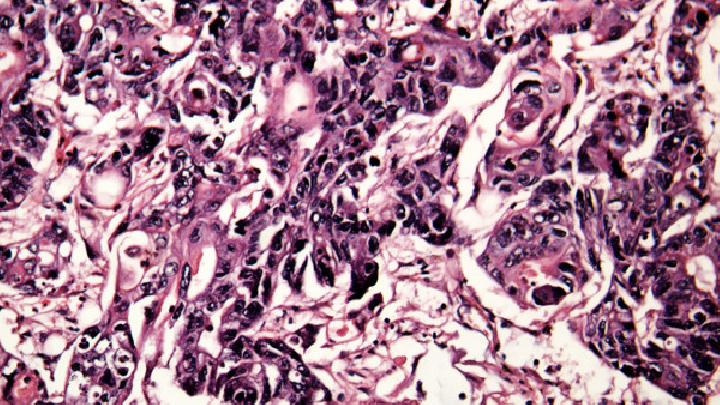

专家最后说:性病,性伴侣必须同时接受检查和治疗,以避免乒乓球感染。性病通常出现在性器官上。除泌尿生殖器外,性病的表现还可能出现在身体的其他器官上,包括皮肤、口腔、眼睛、直肠、肛门和关节。